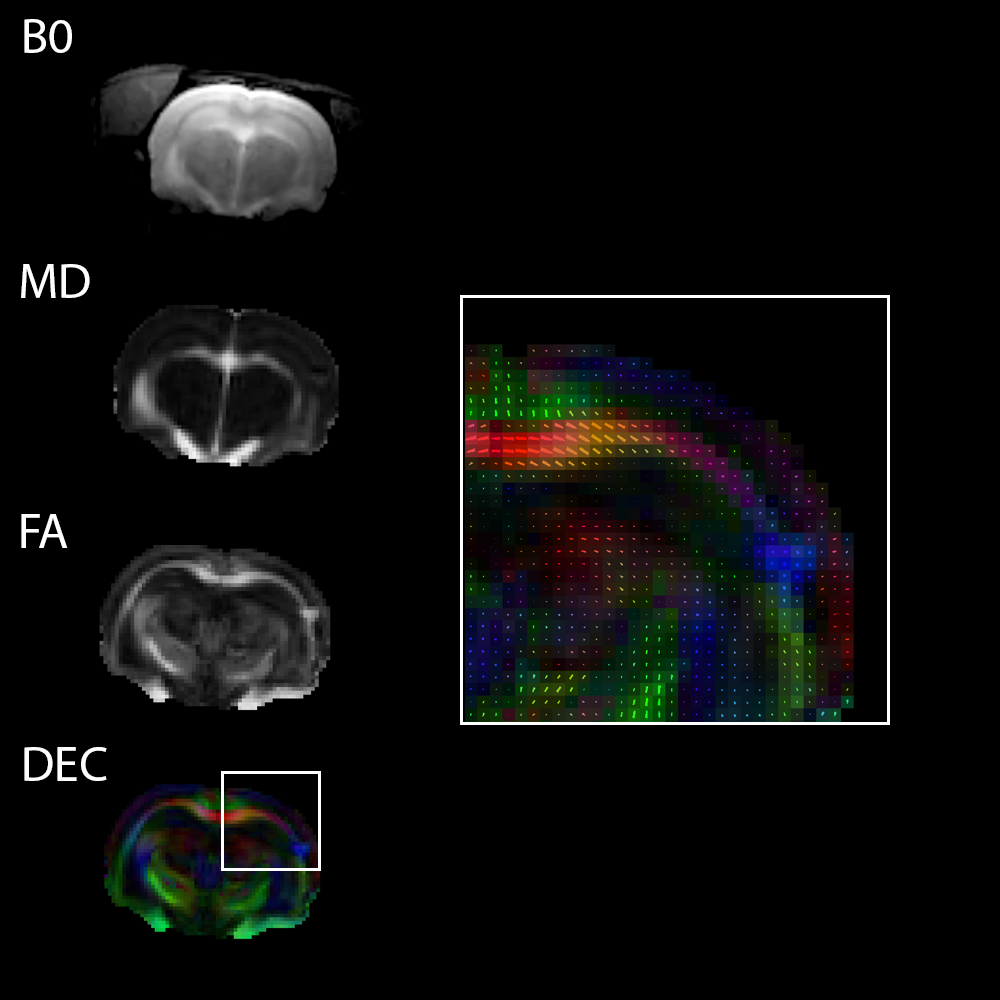

3T磁共振扩散张量成像

大鼠脑组织在3T磁场下进行单次DTI EPI成像

〉动物模型:Wistar大鼠

〉顺序: 单次扫描DTI EPI成像的矩阵尺寸为96×96; 扩散方向的数量为120个;层厚为1毫米。

〉线圈: 用于数据传输的72毫米规格发射/接收用音圈。 用于信号接收的30毫米柔性表面线圈